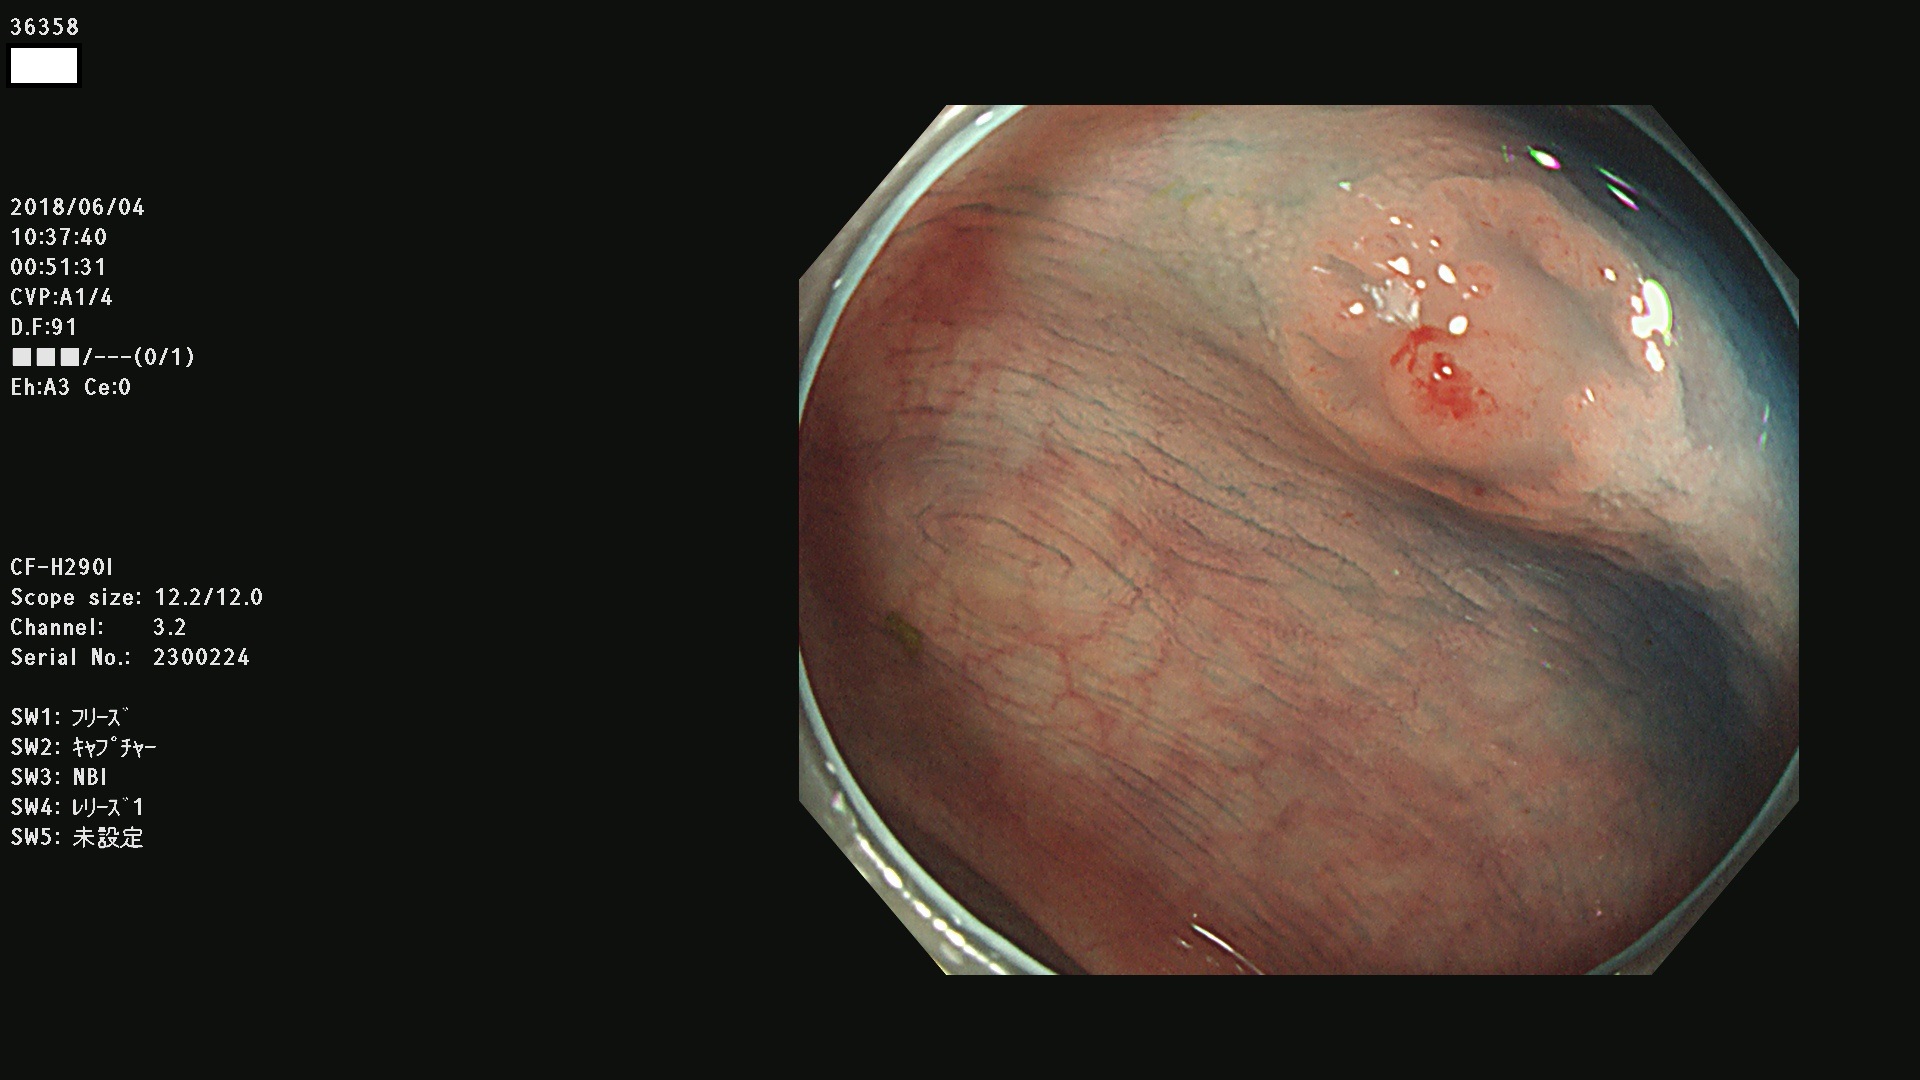

腺腫発見率 68 % (カルテ番号 36300〜36399の100名の方の検査結果で集計)大腸癌検診最新情報

以下のカルテ番号の方に腺腫(Adenoma,Group3〜5)が見つかりました(集計法)

36300 36302 36305 36306 36307 36308 36310 36311 36312 36313 36314 36315 36316 36318 36321 36322 36324 36325 36326 36327 36330 36332 36333 36334 36335(SSAPのみ) 36337 36338 36339(SSAPのみ) 36340 36341 36342(SSAPのみ) 36343 36344 36346 36348 36349 36351 36353 36354 36355(SSAPのみ) 36356 36357 36358 36359 36364 36365 36366 36367 36370 36374 36376 36379 36381 36382 36383 36384 36385 36387 36388 36389 36390 36392 36393 36395 36396 36398 36399

発見困難で危険性の高い平坦型病変(上記100名より抽出) ![]()